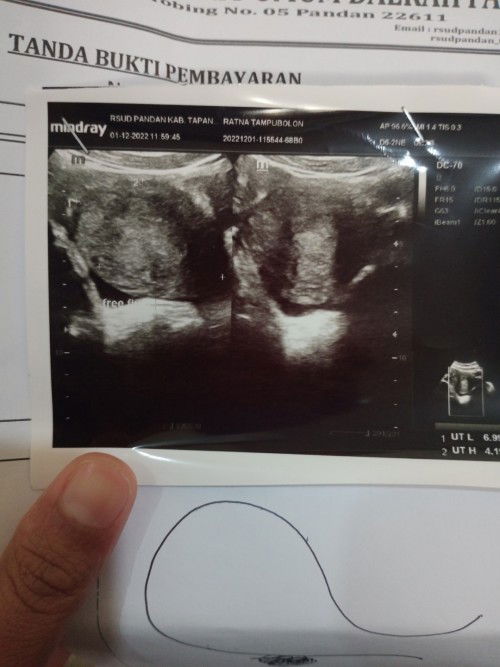

Bun td sya USG ke dokter kandungan, hasilny janin blm kelihatn Dokter menganjurkn utk USG 2mingu lg

cek diusia kandungan 8minggu pasti uda ada janinnya bun.. dulu aku pas 5minggu jg baru keliatan kantong..

rata2 yang hpl nya Agustus semua gtu bund. disuruh balik 2mgg lagi.